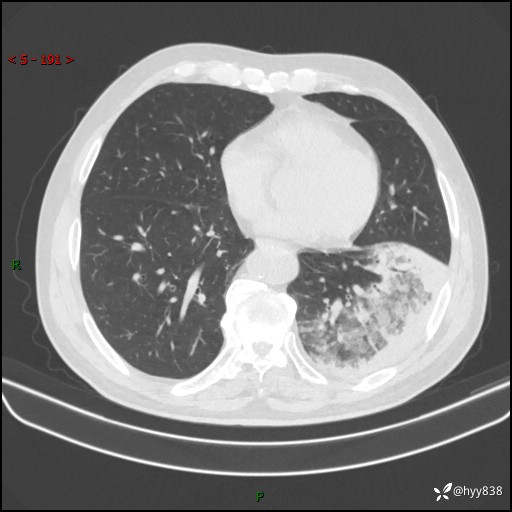

59岁/男,发热伴咳嗽3天。白班偶遇,“大叶性肺炎”,病原体挑战---结果公布~

【患者信息】:59岁/男

【主诉】:发热伴咳嗽3天

【检查】:胸部CT平扫